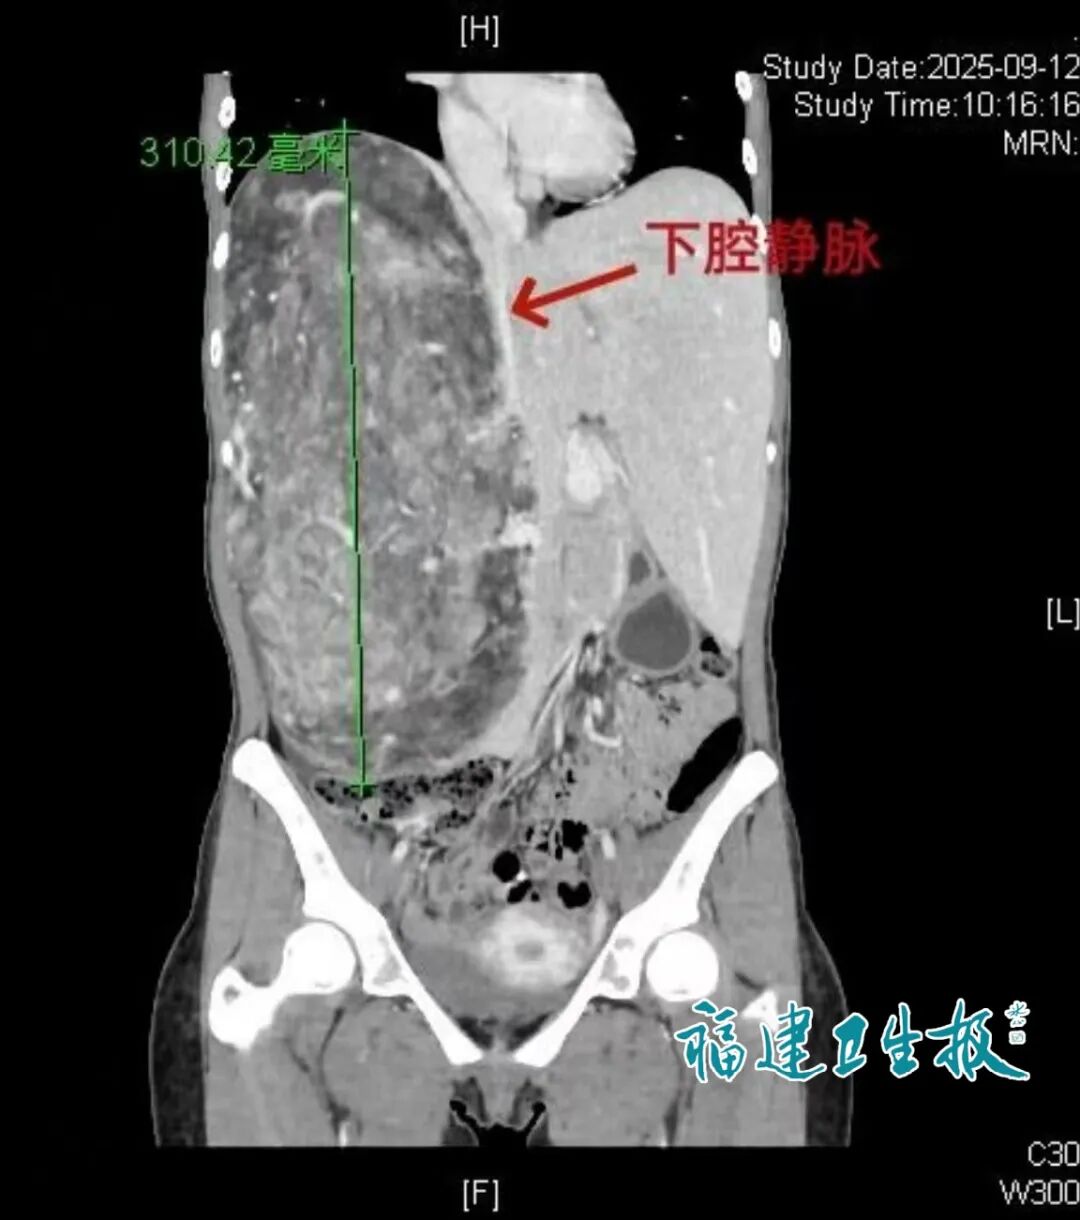

CT检查结果一出来,医生都捏了把汗:她腹腔里的肿瘤直径足有31公分,不仅把右边的肝脏挤得变了形,还死死“卡”住了人体内最大的静脉血管。

更危险的是,长期被肿瘤压迫,她的门静脉已经变成了脆弱的“海绵状血管网”,稍有不慎可能引发大出血。